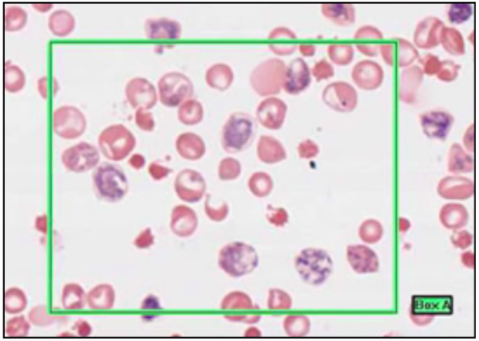

EOSINOPHILS (ROMANOVSKY/LEISHMAN’S)

- 2-3 lobe nucleus

- bright pink granules

- acidophils

- circulate for a few hours

- diurnal - highest in morning

- phagocytose antigen/antibody complexes, associated w/ parasitic infection

- neutralise histamine

GRANULOCYTES

NEUTROPHILS - POLYMORPHONUCLEAR LEUKOCYTES (LEISHMAN’S STAIN)

- multi-lobar nucleus

- most numerous

- phagocytic

- engulf and destroy bacteria

- leave blood stream to enter tissue @ infection site

fine granules = GRANULOCYTES

- primary - lysosomes, acid hydrolases, antibac and digest

- secondary - neutrophil specific, regulation of inflammation response

- tertiary - facilitate insertion of proteis to cell membrane

lobes = 2-4, number increases with age

BASOPHILS - BASOPHILIC LEUKOCYTES

- not multi-lobar

- dark blue granules which appear to fill cell

- least common

- similar role to MAST cells

- secrete HISTAMINE and other vasoactive substances - increased blood flow locally

LYMPHOCYTES

- small cells with dark stained nucleus and little cytoplasm

- B and T are indistinguishable

- immature are bigger than RBC, smaller than granulocytes

- mature roughly equal size to granulocyte

MONOCYTES

- kidney-shaped nucleus

- no granules

- pale blue cytoplasm

- immature cells which differentiate to one of various forms when leave blood and enter connective tissue

- many to macrophages (fixed marcophage @ liver = Kupffer, and @ spleen)

in blood and alveolar air spaces

macrophage phagocytotic, actute inflammation, arrive after neutrophils

PLATELETS

- smaller than red cell

- anucleate

- fragements

- from multinuclear megakaryocytes

- blue

- 4 types of granules:

- alpha - clotting

- dense

- lysosomes

- peroxisomes - elimination of oxygen radicals